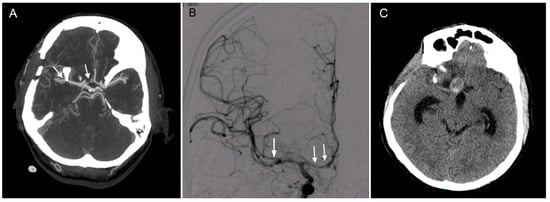

Figure 1.

Clipping of a ruptured middle cerebral artery (MCA) aneurysm complicated in the postoperative course by vasospasm and the development of a pseudoaneurysm (PSA). (A). A computed tomography angiography (CTA) performed on the first postoperative day shows clips after treating an MCA aneurysm (left arrow) and a narrowing of the right A1 segment (right arrow), which eventually led to later complications. (B). Postoperatively, the patient developed a severe vasospasm (white arrows) which was successfully treated including an intra-arterial pharmacological angioplasty with milrinone. (C). Brain computed tomography (CT) performed 3 months later presenting hydrocephalus and a suspicious PSA of the distal right A1 segment.

Postoperatively, the patient developed severe vasospasms, which were successfully treated pharmacologically, including with a one-time pharmacological angioplasty with milrinone. On the fifth postoperative day, a final CTA was performed and demonstrated successful clipping of the ruptured aneurysm without any other vascular anomalies apart from a previously described small mirror aneurysm on the left (Figure 1B). On the 18th postoperative day, the patient was transferred to his local hospital for rehabilitation in good clinical condition—Glasgow coma scale 15, lucid, oriented to place, person and time and a residual minor left-sided hemiparesis accented on the upper limb. Following the transfer, the patient’s clinical condition slowly deteriorated; he became disoriented and showed signs of bradypsychia. A follow-up CT performed 3 months after the surgery showed widening of the ventricles as well as a pseudoaneurysm (PSA) in the distal A1 anterior cerebral artery (ACA) segment (Figure 1C).